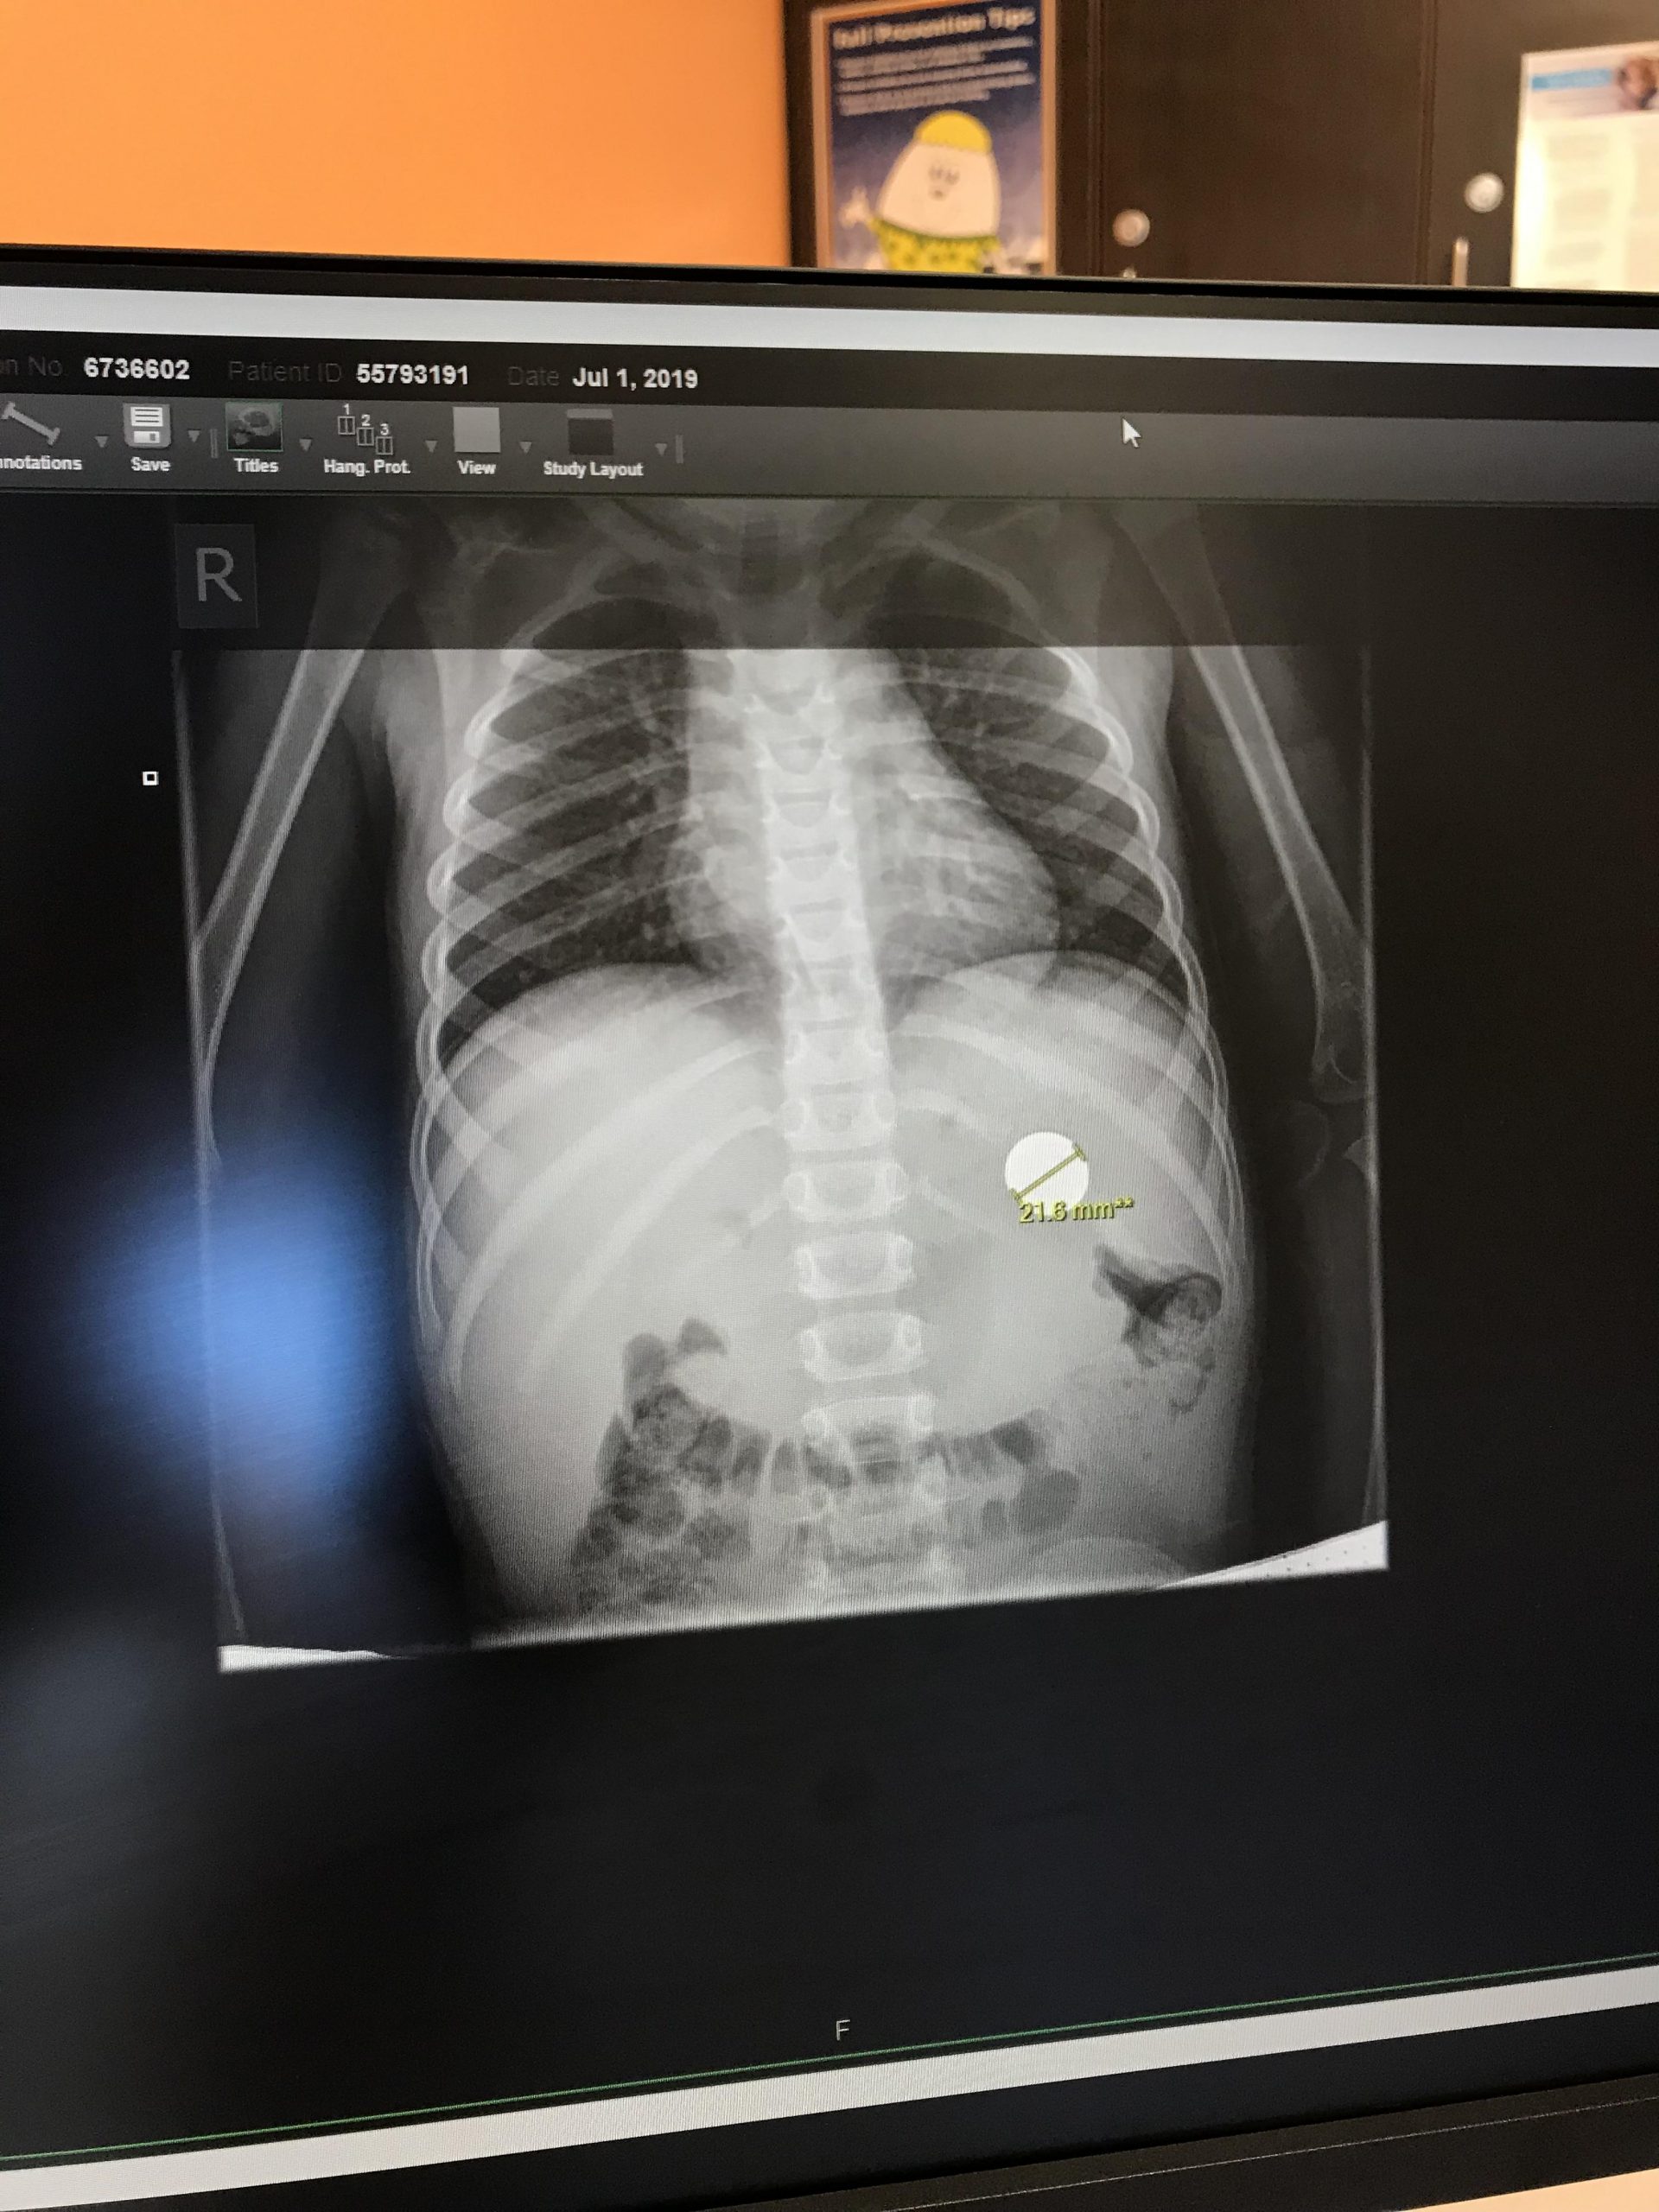

13. «Ahí está la moneda…»